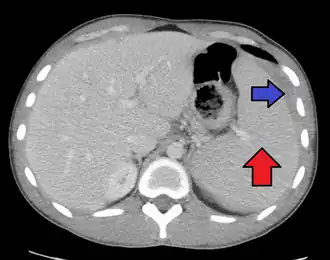

| Complications | Swelling of the liver or spleen[3] |

Infectious mononucleosis (IM, mono), also known as glandular fever, is an infection usually caused by the Epstein–Barr virus (EBV).[2][3] Most people are infected by the virus as children, when the disease produces few or no symptoms.[2] In young adults, the disease often results in fever, sore throat, enlarged lymph nodes in the neck, and fatigue.[2] Most people recover in two to four weeks; however, feeling tired may last for months.[2] The liver or spleen may also become swollen,[3] and in less than one percent of cases splenic rupture may occur.[6]

Spleen enlargement is common in the second and third weeks, although this may not be apparent on physical examination. Rarely, the spleen may rupture.[27] There may also be some enlargement of the liver.[25] Jaundice occurs only occasionally.[16][28]

Physical examination

The presence of an enlarged spleen, and swollen posterior cervical, axillary, and inguinal lymph nodes are the most useful to suspect a diagnosis of infectious mononucleosis. On the other hand, the absence of swollen cervical lymph nodes and fatigue is the most useful to dismiss the idea of infectious mononucleosis as the correct diagnosis. The insensitivity of the physical examination in detecting an enlarged spleen means it should not be used as evidence against infectious mononucleosis.[25] A physical examination may also show petechiae in the palate.[25]

Infectious mononucleosis is generally self-limiting, so only symptomatic or supportive treatments are used.[50] The need for rest and return to usual activities after the acute phase of the infection may reasonably be based on the person's general energy levels.[25] Nevertheless, in an effort to decrease the risk of splenic rupture, experts advise avoidance of contact sports and other heavy physical activity, especially when involving increased abdominal pressure or the Valsalva maneuver (as in rowing or weight training), for at least the first 3–4 weeks of illness or until enlargement of the spleen has resolved, as determined by a treating physician.[25][51]

Observation

Splenomegaly is a common symptom of infectious mononucleosis, and healthcare providers may consider using abdominal ultrasonography to get insight into the enlargement of a person's spleen.[61] However, because spleen size varies greatly, ultrasonography is not a valid technique for assessing spleen enlargement. It should not be used in typical circumstances or to make routine decisions about fitness for playing sports.[61]